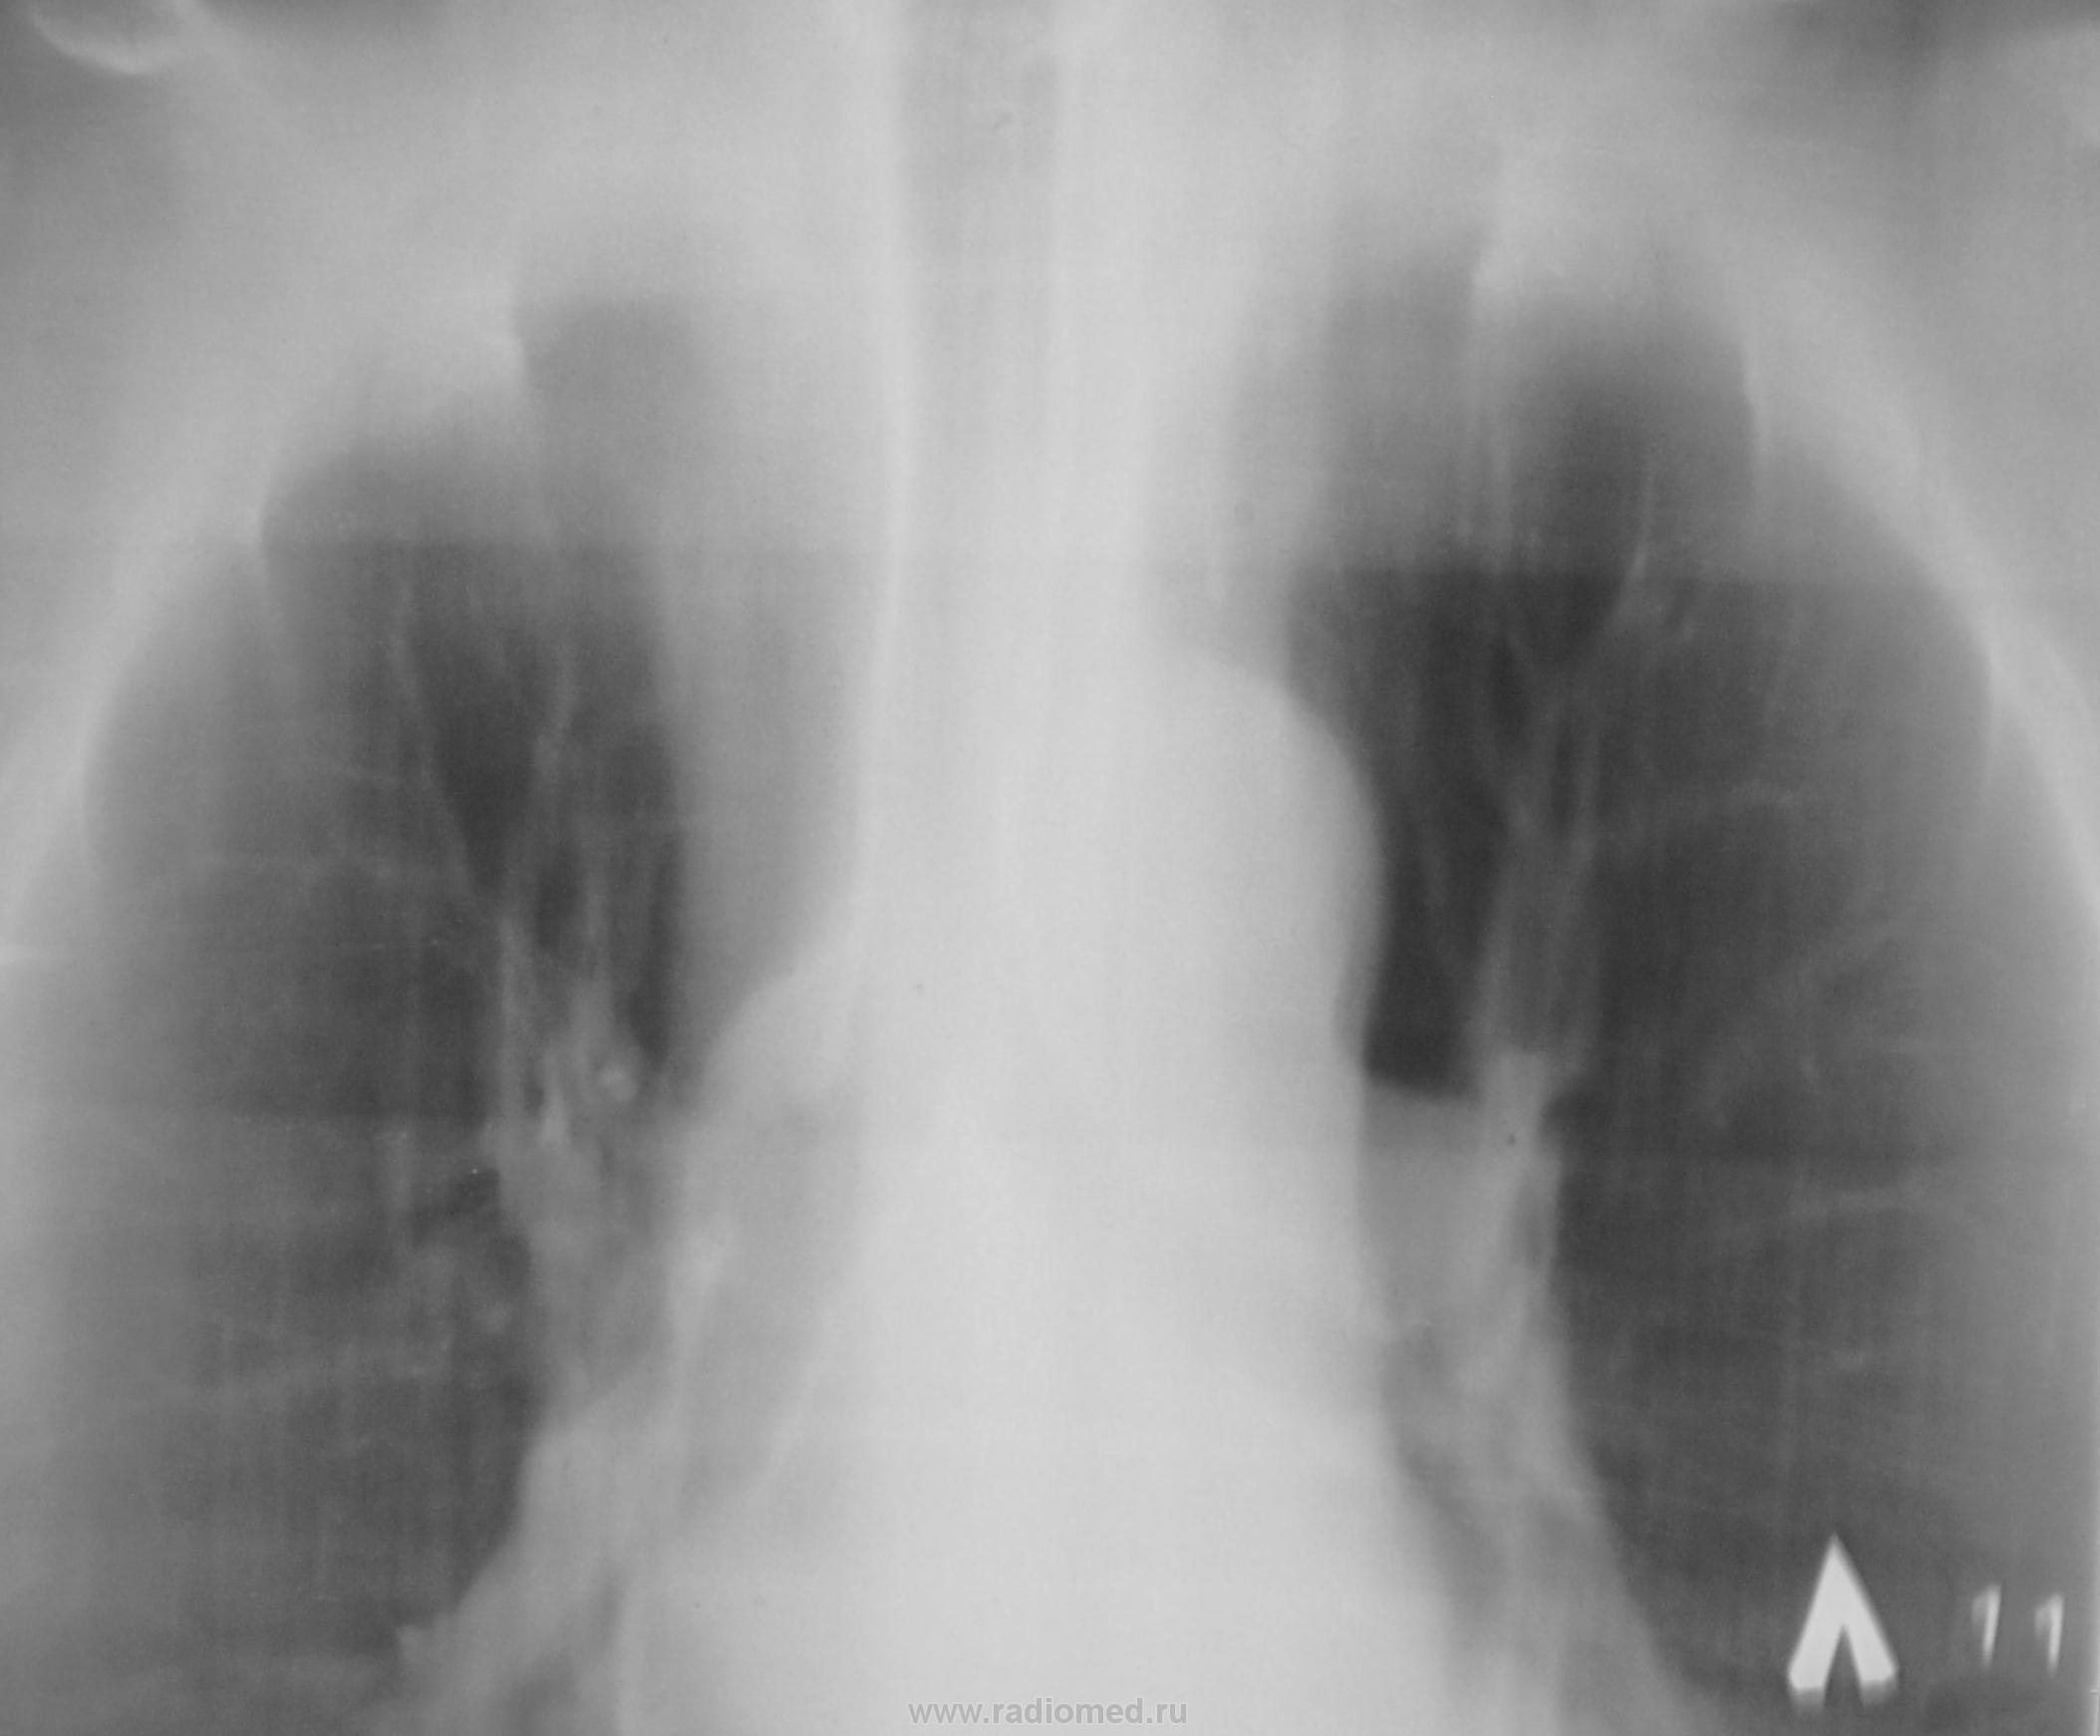

Вроде за правой ключицей очаги, ну и корень справа какой-то некрасивый

Доснять задний снимок верхушек и левый бок(тень за 1 ребром? )

Похоже на очаг Гона. Или просто кальцинат

перенес осложненно протекавший комплекс Ранке справа, т.к.. четко виден очаг Гона, петрификаты в корнях, очаги Симона в верхушках легких. Белая стрелка - мелкая туберкулема с распадом, красный круг - мягкий очаг слева. Только в ПТД! И он Вам поможет.

НО через год гражданин был направлен на очередную профилактическую флюшку..., и с левой верхушки "тихо" улыбаясь на нас глянула "фокусная тень"...